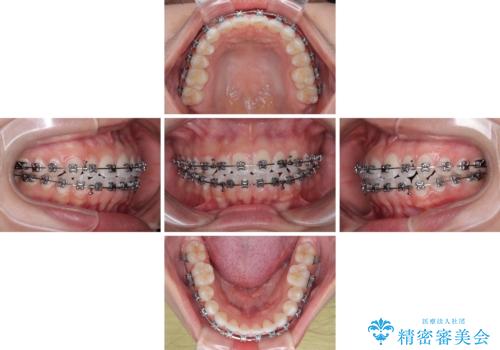

- メタルブラケット

- 上下前歯のデコボコを気にして来院された患者様です。

ワイヤー矯正でもマウスピース矯正でも可能でしたが、短期間で、自身の手を煩わせることなく治療を行いたいとのことで、ワイヤー装置にて矯正治療を行うこととしました。

僅か半年強、あっという間に治療を終えることができました。